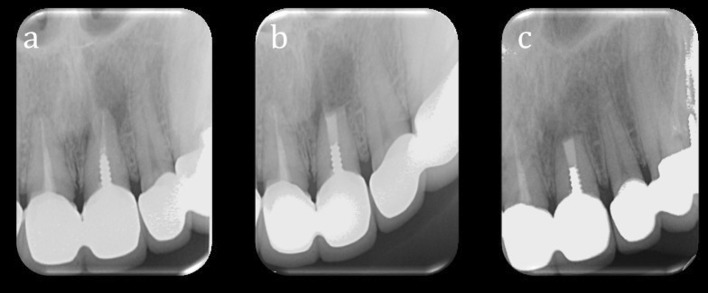

The postoperative radiographs taken at 6 months were evaluated independently by two examiners using the criteria established by Rud et al. [10] (Figs. 2, 3). The two examiners standardized the evaluation criteria before case analyses. Any disagreement regarding the clinical outcome was resolved by discussion until an agreement was reached. The following healing classification was used based on the criteria proposed by Rud et al. [10]:

Fig. 3.

Preoperative (a), immediately postoperative (b) and 6 months postoperative (c) periapical radiographs of another patient included in this study